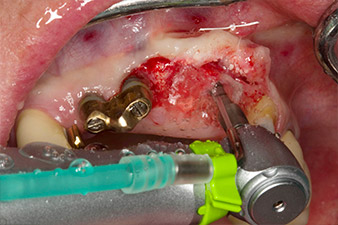

Nach primärer Abheilung werden die Weichgewebe mithilfe der basal unterfütterten Brücke ausgeformt. Zwei Monate später erfolgt die Freilegung mit einem leicht palatinal gelegten Kieferkammschnitt (Abb. 2).

Der Alveolarknochen erweist sich an Position 22 als ausreichend dimensioniert. Die Abbildungen 2 und 4 zeigen die Implantatbett-Aufbereitung, den Gewindeschnitt und die Implantation mit dem Implantmed.